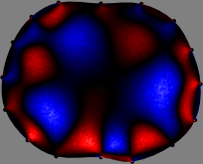

Figs. 3 and 4 compare the performance of the proposed FER method in (20) with the standard regularized least-squares method ((19) when \mathcal{R} is the identity matrix). The regularization parameter of the standard method was heuristically chosen for its best performance, and the parameter of the FER method was set to be one of three different values λ=0.05,0.2,𝜆0.050.2\lambda=0.05,0.2,\infty. The injection current was 1 mARMSRMS{}_{\tiny{\mbox{RMS}}} at 100 kHz, and the frame rate was 9 frames per second. The reference frame at t0subscript𝑡0t_{0} was obtained from the maximum expiration state. The measured data, 𝐕˙(tm)˙𝐕subscript𝑡𝑚\dot{\mathbf{V}}(t_{m}), represent the voltage differences between each time tmsubscript𝑡𝑚t_{m} and t0subscript𝑡0t_{0}. The blue regions, which denote where conductivity decreased by inhaled air, increased during inspiration and decreased during expiration. The FER method with λ=𝜆\lambda=\infty was clearly more robust than the standard method that produced more artifacts originated from the inversion process.

Figure 4: The reconstructed images of the conductivity change of the subject B by the standard regularized least square method and the proposed fidelity-embedded regularization (FER) method for three difference values λ=0.05,0.2,𝜆0.050.2\lambda=0.05,0.2,\infty. Here, the time step is 0.55 seconds (tm+5tm0.55subscript𝑡𝑚5subscript𝑡𝑚0.55t_{m+5}-t_{m}\approx 0.55).